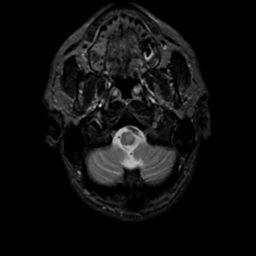

MR Study #8, March 31, 1991 -- Slice #4